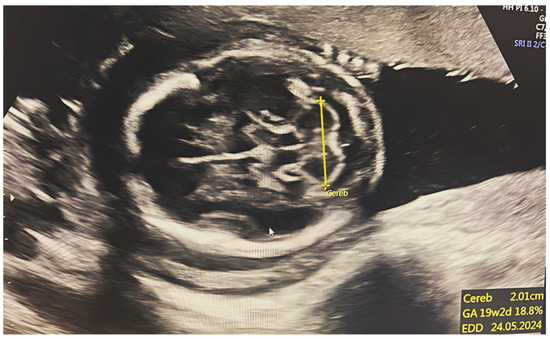

2.2. Ultrasonography

2.3. TCD Measures